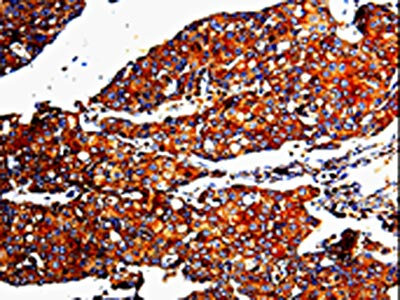

• The image is immunohistochemistry of paraffin-embedded Human breast cancer tissue using CSB-PA014205(MMP3 Antibody) at dilution 1/10. (Original magnification: ×200)

• The image is immunohistochemistry of paraffin-embedded Human cervical cancer tissue using CSB-PA014205(MMP3 Antibody) at dilution 1/10. (Original magnification: ×200)